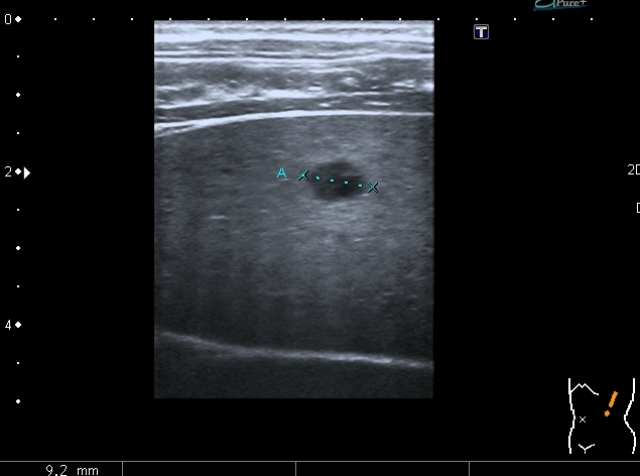

"Плохой"  подмышечный лимфатический узел, но справа. "Bad" axillar LN is seen